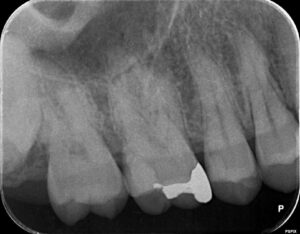

他院で治療をしてもらったが、痛みがずっと続く、ということで当院に来られました。診査の結果、右上6番目の歯の神経が細菌感染を起こしているため、痛みが続いているとわかりました。そこで、2回に分けて、根管治療と修復処置を行いました。

横の右上5番目の歯は神経近くまで虫歯は進んでいましたが、神経を保存することが出来ました。